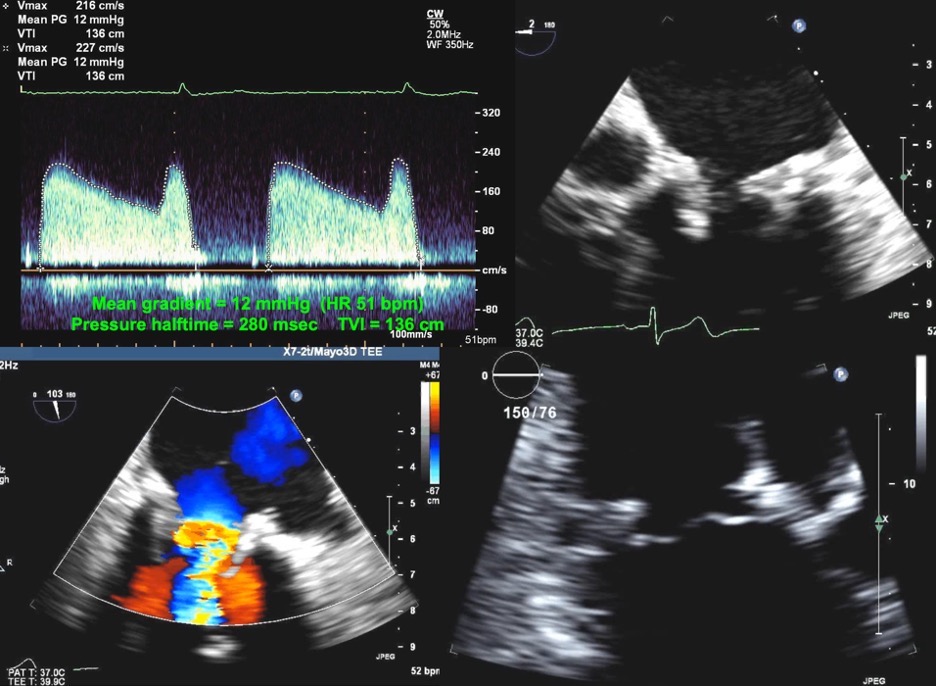

Fig. 8.Echocardiographic imaging of a patient with a mitral bioprosthesis and prosthetic dehiscence. Top Left and Right: Continuous Wave Doppler of a male

with a Biocor porcine mitral bioprosthesis just 5 months previously. The mean

gradient was 11 mmHg with a heart rate of 51. The DVI was 4.0, with an EOAi of

0.48 cm